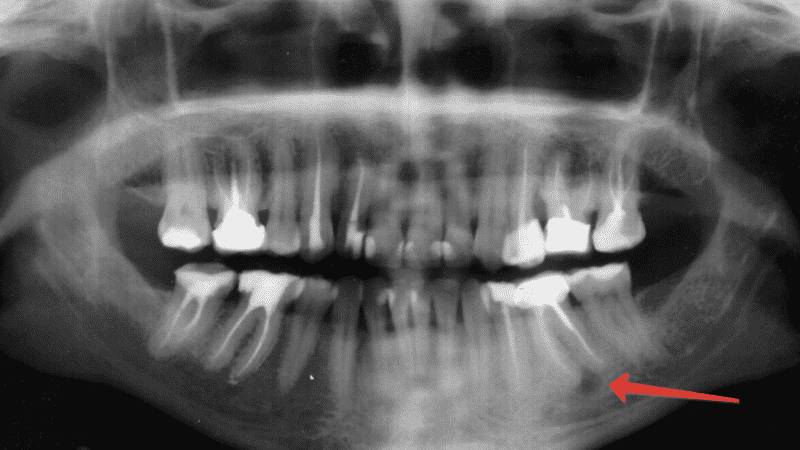

Киста может располагаться в любой части ротовой полости. Ее развитие происходит медленно, начиная с воспаленного очага, который приводит к образованию полости, заполненной гноем. Диагностировать кисту на этом этапе можно только с помощью рентгена или в процессе лечения других заболеваний десен и зубов, таких как гингивит, кариес, пульпит и пародонтоз.